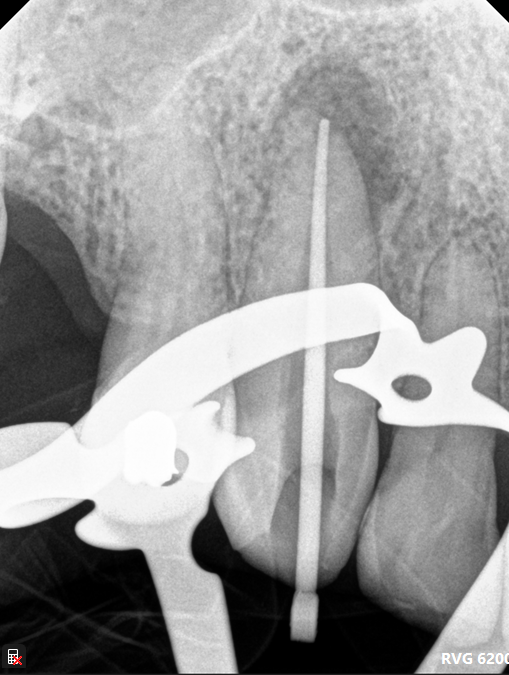

Case: RCT on Tooth #19

35-year-old female, Spanish-speaking, no past medical history.

Dx: Pulp necrosis and symptomatic apical periodontitis with PARL (#19).

Tx: Root canal therapy.

Reflection

The main challenge was the patient’s TMJ discomfort—she had trouble keeping her mouth open and needed multiple breaks. CBCT showed the mesial canals were converging apically, which helped guide shaping. Unfortunately, the distal canal appeared slightly overextended on the final image, reminding me of the importance of precise working length control, especially in cases with limited access.